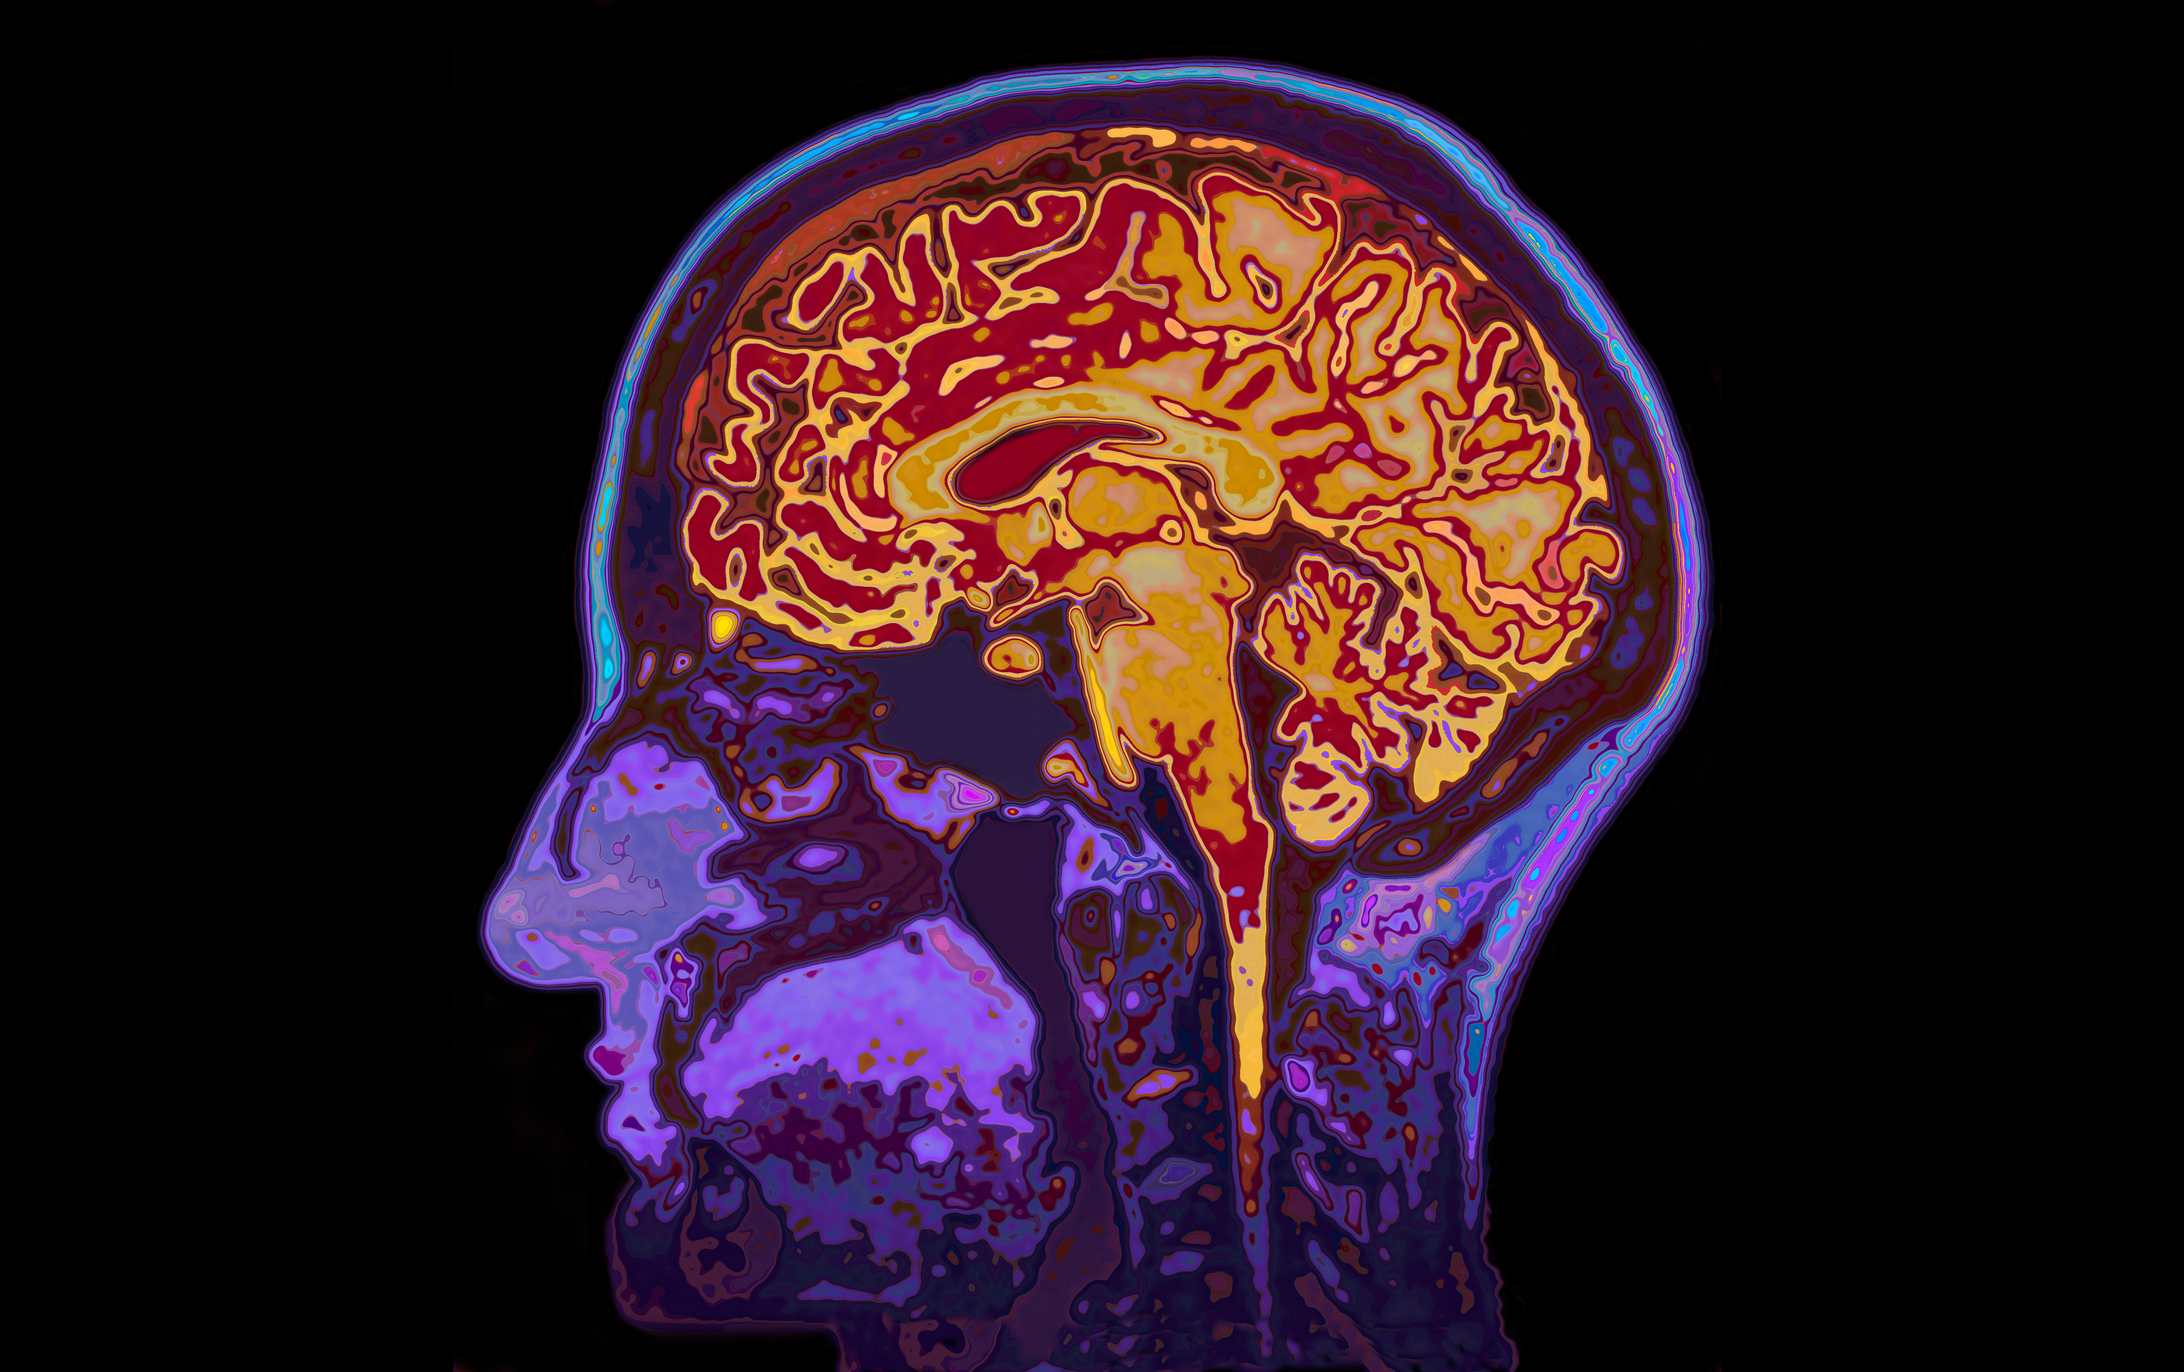

Durante mucho tiempo se creyó que el cerebro humano alcanzaba su madurez alrededor de los 18 o 25 años. Sin embargo, una investigación reciente de la Universidad de Cambridge propone una visión muy distinta: nuestro cerebro no “entra en la adultez” hasta aproximadamente los 32 años, y atraviesa cuatro momentos clave de reorganización a lo largo de la vida.

Los científicos explican que el cerebro no es un órgano estático que madura y se detiene, sino un sistema dinámico que continúa reajustándose durante décadas.